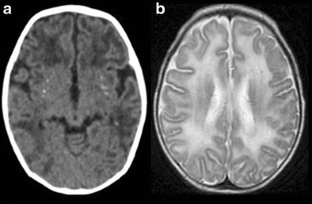

Fig. 1